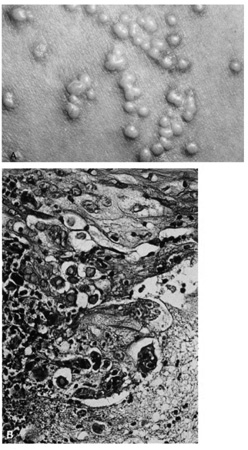

Lesions of molluscum contagiosum often affect the periorbital and lid skin as 1- to 3-mm domeshaped papules with a small central dell. This large pox virus multiplies in the cytoplasm, and, histologically, homogeneous purple intracytoplasmic inclusion bodies (molluscum bodies) are seen in an acanthotic epidermis (see Fig. 7).

Fig. 7. Molluscum Contagiosum—A. Umbilicated lesions typical of molluscum contagiosum on the upper lid of a child. Infection near the edge of the lid may cause a toxic follicular conjunctivitis. B. Low-power photomicrograph demonstrating crater shape of excised lesion (hematoxylin and eosin stain). C. High-power photomicrograph illustrating the large clumps of eosinophilic viral inclusions in the epithelial cells (“molluscum bodies“) (hematoxylin and eosin stain). (Photos courtesy of William Morris, M.D.)